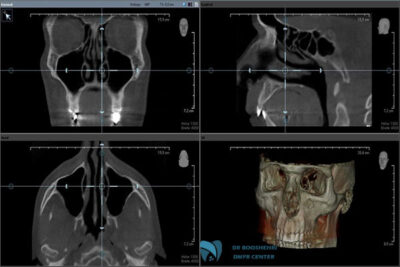

Moreover, hands-on training for specialists, particularly in the use of advanced devices, plays a crucial role in improving imaging quality. The use of modern technologies, such as 3D imaging, can also enhance accuracy and detail, addressing many common mistakes in the process.

Dr. Bushahri, a specialist in oral, jaw, and maxillofacial radiology, with years of experience and the use of the most advanced imaging equipment, is ready to provide you with the best services. At his specialized center, you can benefit from high quality, precise diagnosis, and expert consultations. If you’re looking for precise and error-free imaging, it’s time to contact Dr. Bushahri’s specialized imaging center for a consultation and book your appointment.